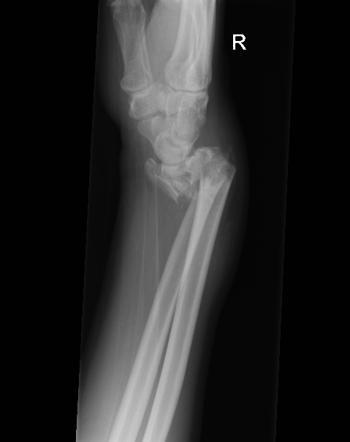

What is a Barton’s fracture?

Intra-articular fractures of the distal radius involving dorsal or volar rims

Carpal bones of the wrist sublux with the displaced rim fragment

What are the two classifications of Barton’s fractures?

What is the treatment for a Barton’s fracture?

ORIF